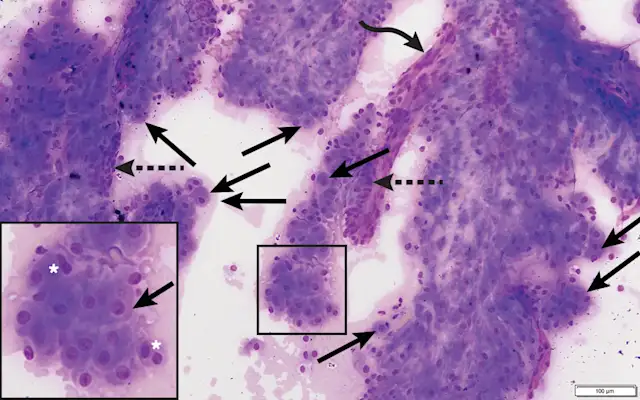

Cytology

Cytologic assessment (Figures 2 and 3) resulted in diagnosis of perianal gland neoplasia (ie, hepatoid tumor). Excisional biopsy with histopathology was recommended to determine whether the tumor was malignant or benign. Tumor staging via thoracic radiography, abdominal radiography, and abdominal ultrasonography were considered but not performed due to owner financial constraints.

On cytology, perianal gland adenomas have a predominant population of large, cuboidal- to polygonal-shaped epithelial cells found in cohesive cell clusters with granular, pink–blue cytoplasm. Nuclei are round, usually single, with distinct nucleoli. Cellular pleomorphism is minimal.3 Varying numbers of reserve (basaloid) cells are also typically present, but the proportion of reserve cells is not an indicator of biological behavior.9 Tumors predominantly composed of reserve cells (>90%) are classified as epitheliomas.8